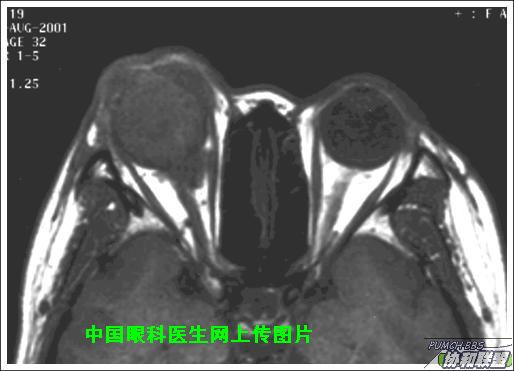

出院后半年发现右眼出现肿物,增长较快,随来京再次就诊(图1),转来我科。门诊检查发现:右眼无光感,结膜下肿物,突出睑裂。眼球突出,上移位。眶外侧可触及硬性肿物。超声(图2),CT(图3),MRI(图4,5,6)显示如图.